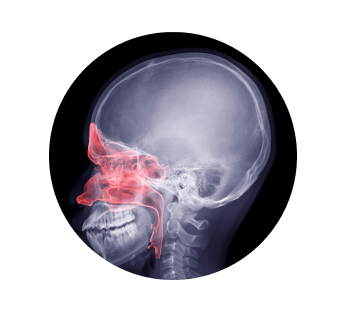

Рентген пазух носа в Краснодаре

Рентген пазух носа назначается врачом, если у пациента присутствуют такие симптомы как заложенность, припухлости, при подозрении на присутствие инородных тел (актуально для детей), если часто идет кровь из носа, при жалобах на боль в лицевой части без видимых причин. Процедура позволяет выявить возможные патологии и диагностировать различные заболевания.